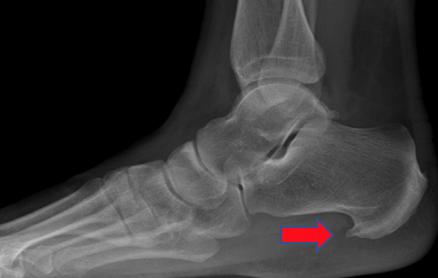

跟骨骨刺关节镜下切除术前